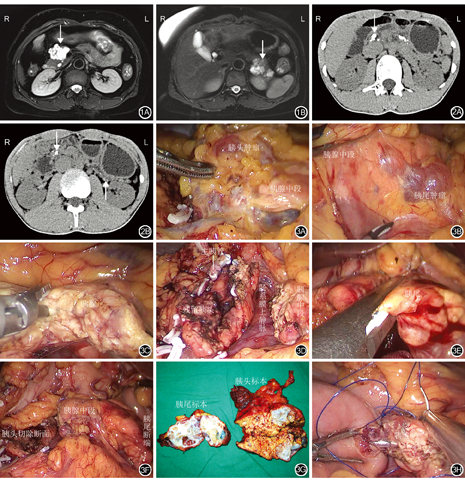

病例1为52岁女性患者,因健康体检发现胰腺占位性病变20 d,于2019年9月收入我院。患者体格检查和实验室检查均无异常表现,血清肿瘤标志物检测均正常。患者术前MRI检查结果示胰头、胰尾多发不规则多房囊性占位性病变,其内可见多发分隔,胰头肿瘤大小约为5 cm×5 cm,胰尾肿瘤融合成团,范围约为4 cm×4 cm,考虑为浆液性囊腺瘤可能;肝多发囊肿(图1A,图1B)。术前诊断:胰腺占位性病变,浆液性囊腺瘤、肝多发囊肿待查。

病例2为20岁男性患者,因反复腹上区疼痛1个月余,于2019年7月收入我院。患者体格检查和实验室检查均无异常表现,血清肿瘤标志物、血清淀粉酶检测均正常。患者术前CT检查结果示胰管多发结石,最大径约为1.4 cm,伴胰管不均匀扩张,考虑为慢性胰腺炎改变(图2A,图2B)。术前诊断:慢性胰腺炎、胰管多发结石。

病例1于2019年9月17日在全身麻醉下行腹腔镜胰头肿瘤切除+胰体尾切除+脾切除+胰肠吻合术。术中探查:胰头及胰体尾部可见多发肿瘤隆起于胰腺表面,呈多房囊液状,部分融合成团,最大病灶位于胰头处约为5 cm×5 cm×4 cm,与周围组织明显致密粘连(图3A,图3B)。术者先解剖胰腺颈部下缘及上缘,建立胰后隧道,于胰颈处横断胰腺(图3C),主胰管直径约为0.4 cm。予超声刀联合电凝刀仔细分离粘连,距离胰头肿瘤1 cm处完整切除(图3D)。超声刀游离胰体尾下缘,仔细分离胰体尾部肿瘤,胰尾肿瘤大小约为4 cm×4 cm×3 cm,与脾动、静脉粘连致密,难以分离,遂距离胰尾肿瘤3 cm行胰体尾切除联合脾切除术(图3E)。胰腺远切端予3-0 prolene连续缝合关闭。保留胰腺中段约8 cm(图3F)。剖开标本见胰头及胰尾肿瘤均为多房囊性,切开见透明液体流出,内见多发分隔,未见乳头状肿瘤形成(图3G)。胰头及胰体尾肿瘤术中冷冻切片组织病理学检查结果示胰腺浆液性囊腺瘤。距离屈氏韧带约15 cm离断空肠,将空肠远切端与胰管近端行端侧吻合术(结肠后),距胰肠吻合口约50 cm处空肠与近端空肠行肠肠吻合术(图3H)。

病例2于2019年7月25日在全身麻醉下行保留十二指肠全胰头切除+保留脾脏胰尾切除+胰管切开取石+胰肠侧侧吻合术。术中探查:胰腺呈慢性胰腺炎改变,质地坚硬,全胰可扪及多发质地坚硬结石,以胰头最多,结石最大约为1.0 cm×1.0 cm。先解剖胰腺颈部下缘及上缘,建立胰后隧道,于胰颈处横断胰腺,见主胰管明显扩张,直径约为1.5 cm。予3-0丝线双重结扎并离断胃网膜右动脉,游离并悬吊胃十二指肠动脉。紧贴肠系膜上动脉右侧缘离断胰腺钩突系膜,紧贴胰头下缘及右侧缘分离,完整保留胰十二指肠前、后动脉弓及胆总管,完整切除胰头(图4A,图4B)。沿主胰管纵行切开胰体尾,见主胰管及分支胰管内多发结石,最大约为1.5 cm×1.0 cm。探查见胰尾部萎缩,长约3 cm,内有较多结石,难以取尽,遂决定切除胰尾。胰尾断端予3-0 prolene连续缝合关闭。保留长度约8 cm中段胰腺(图4C)。距离屈氏韧带约15 cm离断空肠,将空肠远切端与胰管切口行侧侧吻合术(结肠后),距胰肠吻合口约50 cm处空肠与近端空肠行肠肠吻合术。剖开胰头及胰尾标本见胰腺质地坚硬,主胰管及分支胰管内见多发细小结石(图4D)。

病例1和病例2均顺利完成MPP,手术时间分别为470 min和400 min;术中出血量分别为200 mL和100 mL;2例患者术中均未输血。病例1和病例2术后血糖分别为5.4~11.8 mmol/L和5.9~11.3 mmol/L。病例1术后发生腹腔感染,经抗感染治疗后好转出院;病例2术后恢复顺利,无并发症发生。病例1和病例2均无胰瘘及围术期死亡;术后住院时间分别为12 d和8 d。病例1术后胰腺标本组织病理学检查结果示胰头、胰尾浆液性囊腺瘤(图5)。病例2术后胰腺标本组织病理学检查结果示胰头、胰尾组织胰管轻度扩张伴多发结石,胰管周围慢性炎症细胞浸润(图6)。病例1和病例2例术后复查CT示保留胰腺长度分别为8.5 cm和8.3 cm(图7,图8)。病例1和病例2例均获得随访,随访时间分别为5个月和7个月。随访期间2例患者均无新发糖尿病,无需胰酶替代治疗。2例患者均于术后5个月行腹上区CT平扫及增强复查,中段胰腺血运良好,无肿瘤及结石复发征象。